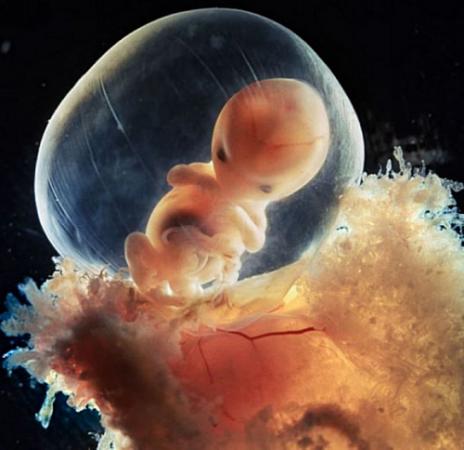

3、内窥镜成像

这是科学家用内窥镜拍摄的8周大的胎儿。快速发育的胎儿在胎囊内受到很好的保护。

内窥镜是一个配备有灯光的管子,它可以经口腔进入胃内或经其他天然孔道进入体内。利用内窥镜可以看到X射线不能显示的病变,因此它对医生非常有用。